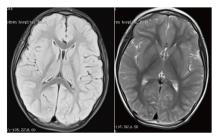

目的 探讨TRIT1基因变异导致联合氧化磷酸化缺陷症35型(COXPD35)患儿的临床特征,从而提高临床医师对于此疾病的认识。方法 回顾性收集3例TRIT1复合杂合变异所致COXPD35患儿,总结其临床资料、辅助检查、基因检测结果、诊治过程,并进行相关的文献复习。结果 3例TRIT1所致COXPD35型患儿均为男性儿童,起病年龄从5月龄到2岁3个月,均以热性惊厥起病,以后逐渐出现肌阵挛发作,并发展为难治性癫痫。3例患儿均存在小头畸形、智力障碍和锥体束征,血液乳酸水平无明显增高。3例患儿共发现3个基因变异位点,其中c.172-2A>T和c.741G>A既往文献未报道。结论 TRIT1所致COXPD35往往以热惊厥起病,之后出现多种发作类型,肌阵挛发作为主且不易控制。患者婴儿期可能发育里程碑正常,癫痫发作后开始出现精神发育倒退,小头畸形和锥体束征常见,乳酸往往不升高。

Objective To investigate the clinical characteristics of patients with combined oxidative phosphorylation deficiency type 35(COXPD35) caused by TRIT1 gene mutations, in order to enhance clinicians' understanding of this disease. Methods A retrospective analysis was conducted on three patients diagnosed with COXPD35 resulting from compound heterozygous variants in the TRIT1 gene. Clinical data, auxiliary examinations results, genetic findings, and diagnostic courses were summarized and reviewed alongside relevant literature. Results All three patients were male children, with onset ages ranging from 5 months to 2 years and 3 months. They all presented initially with febrile seizures, which were later followed by myoclonic seizures and eventually progressed to refractory epilepsy. Common clinical features included microcephaly, intellectual disability, and pyramidal tract signs. Blood lactate levels were not significantly elevated. Genetic testing identified three TRIT1 mutation sites, among which c.172-2A>T and c.741G>A have not been previously reported in the literature. Conclusions COXPD35 caused by TRIT1 mutations typically begins with febrile seizures, followed by various seizure types, predominantly difficult-to-control myoclonic seizures. Patients may achieve normal developmental milestones during infancy, but experience psychomotor regression after seizure onset. Microcephaly and pyramidal tract signs are common, while lactate levels often remain normal.